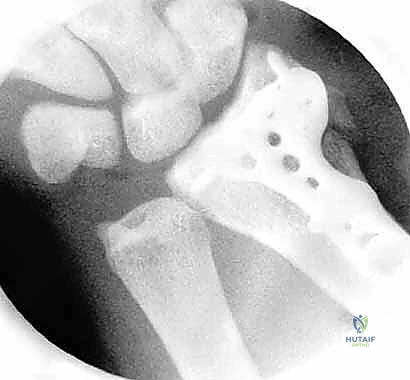

الخطوة الخامسة: التثبيت الداخلي

بمجرد استعادة الشكل التشريحي، يتم تثبيت العظام. قد يتم استخدام أسلاك كيرشنر (K-wires)، مسامير دقيقة، أو شريحة معدنية داعمة (Volar Plate) توضع من خلال شق صغير منفصل لضمان ثبات الكسر التام. يتم أيضاً خياطة أي تمزق في الأربطة إن وجد.

الخطوة السادسة: الإغلاق

تُغلق الثقوب الصغيرة بغرزة واحدة أو بشريط لاصق طبي، وتوضع جبيرة خفيفة لدعم الرسغ في الأيام الأولى.

- التأكد من التئام العظم عبر الأشعة السينية.